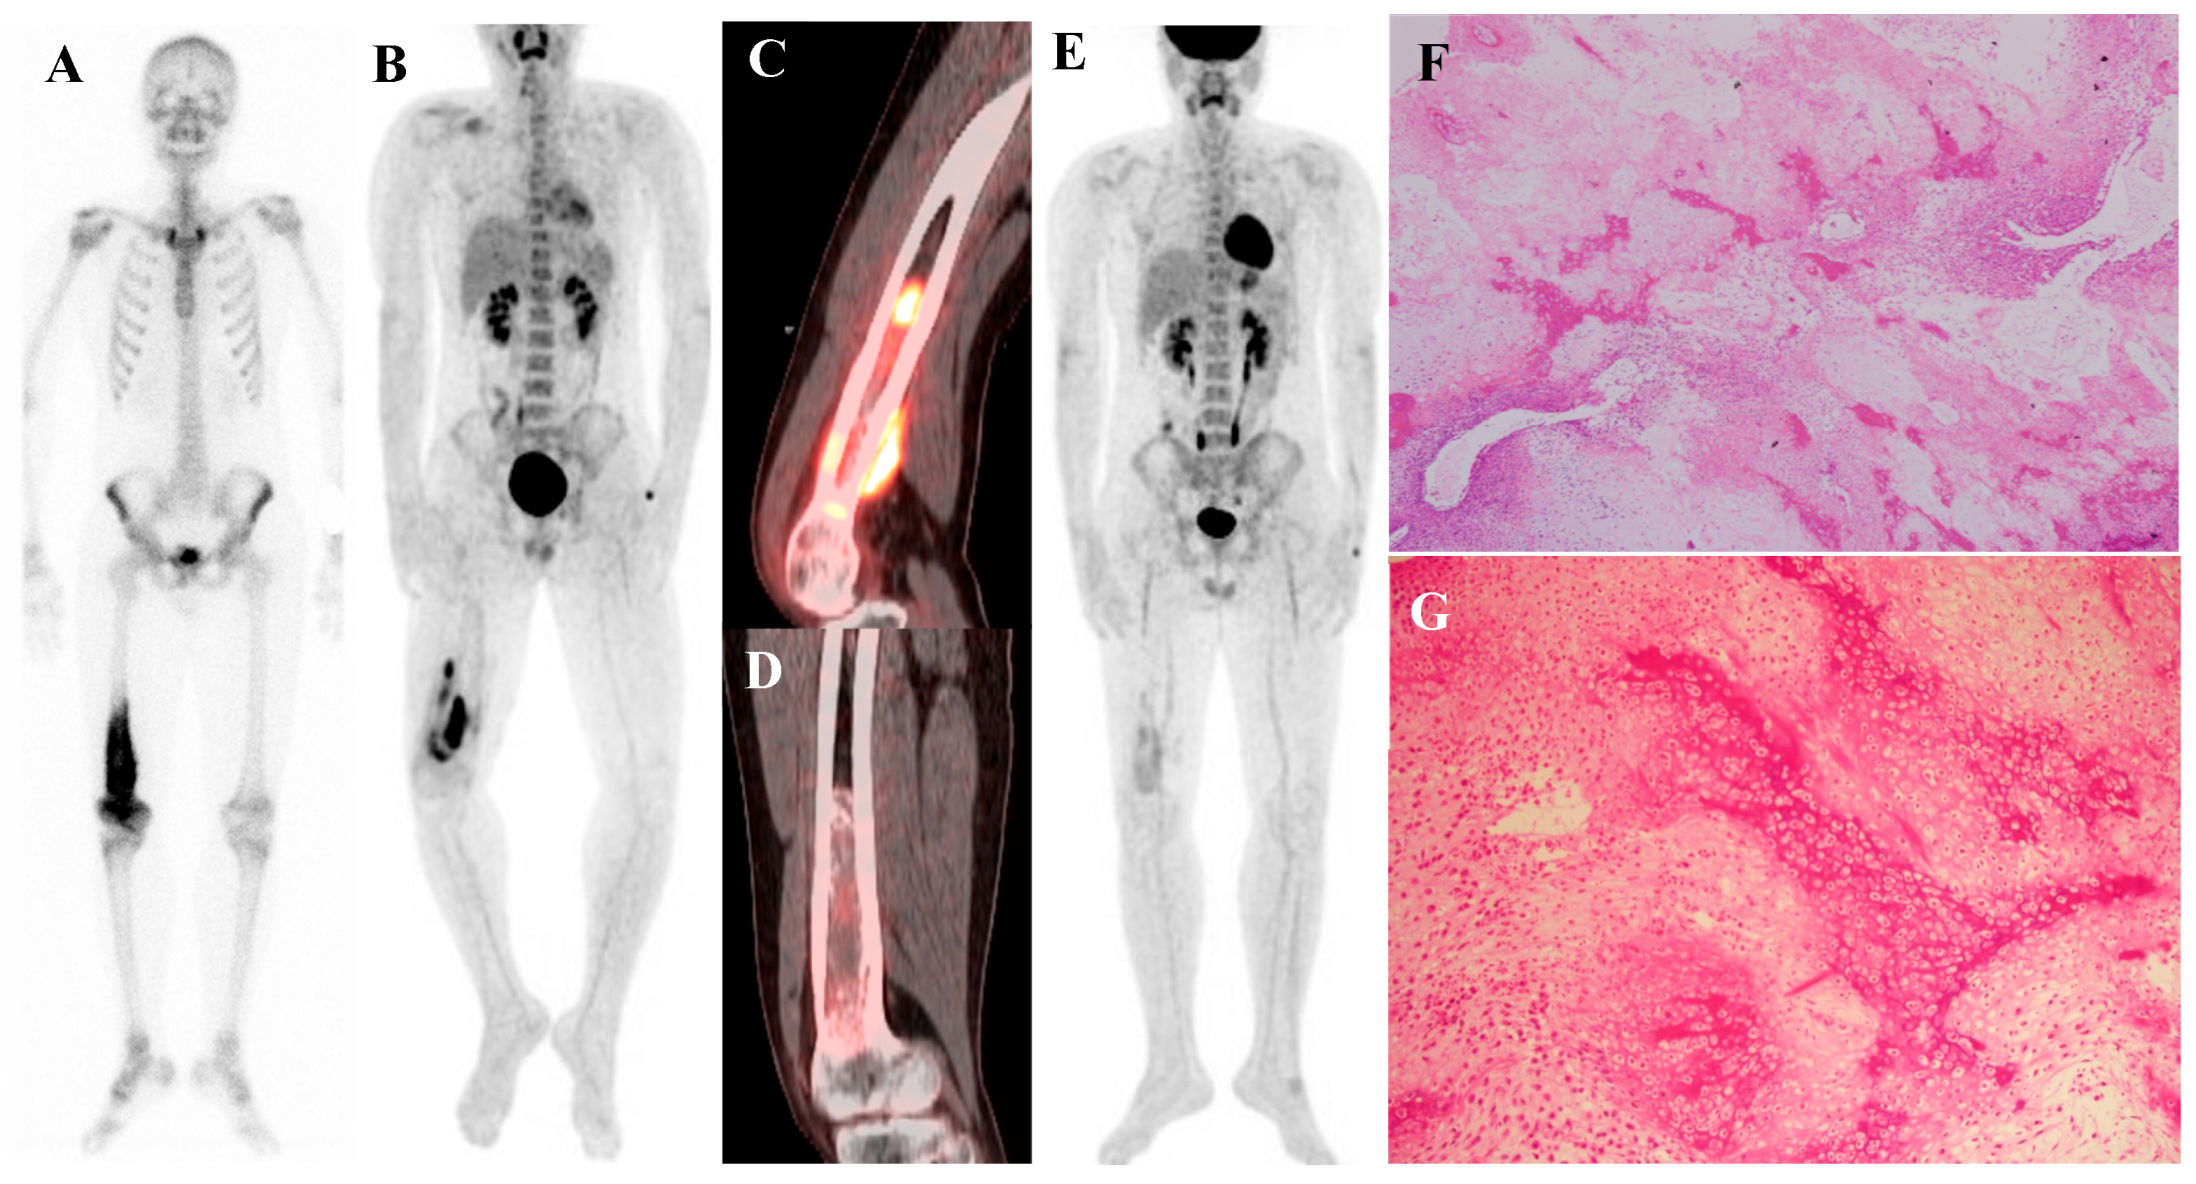

Perhaps the most critical role for [18F]FDG PET/CT in osteosarcoma management is in the evaluation of response to neoadjuvant chemotherapy. The standard of care for high-grade osteosarcoma involves preoperative chemotherapy followed by surgical resection. The degree of tumor necrosis in the resected specimen is one of the most powerful prognostic factors. A “good response,” defined as ≥90% tumor necrosis, is associated with a much better prognosis than a “poor response” (<90% necrosis). [18F]FDG PET/CT perfor-med before and after neoadjuvant chemotherapy can non-invasively predict this histologic response. A significant reduction in the tumor’s SUVmax following chemotherapy is a robust indicator of a good pathologic response [15,37,38,39,40,41,42,43]. This information can help predict prognosis and guide critical therapeutic decisions. Figure 1 demonstrates a representative case in which marked reduction of [18F]FDG uptake after chemotherapy corresponded to predominantly necrotic tissue in the resected specimen, resulting in long-term disease-free survival. This information can help predict prognosis and guide critical therapeutic decisions.

Figure 1.

A 16-year-old male with osteosarcoma of the right distal femur. (A) Pretreatment bone scintigraphy shows intense uptake in the distal femoral metaphysis. (B,C) Pretreatment [18F]FDG positron emission tomography/computed tomography demonstrates a heterogeneous, [18F]FDG-avid mass with cortical breakthrough and soft-tissue extension (SUVmax 12.6). (D,E) After neoadjuvant chemotherapy, [18F]FDG uptake markedly decreased (SUVmax 2.3) with reduction in tumor extent. (F) Wide excision specimen (×40) revealed predominantly necrotic tissue, confirming a marked response to chemotherapy, in contrast to (G) the pretreatment biopsy specimen (×100) with viable malignant cells. He has remained disease-free for 8 years.